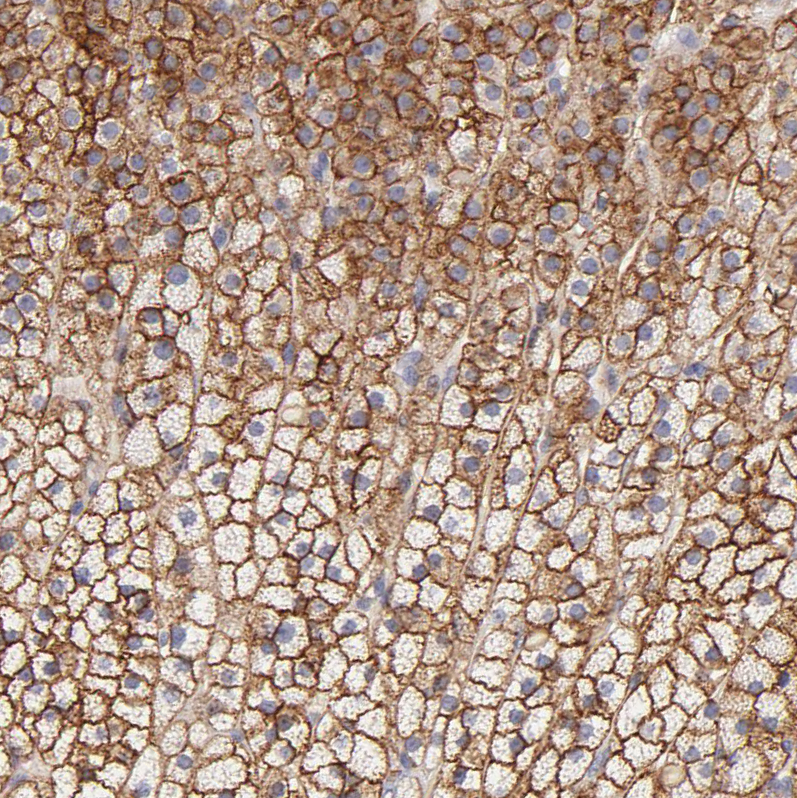

Immunohistochemical staining of human kidney shows moderate positivity in apical membrane in cells in distal tubules.